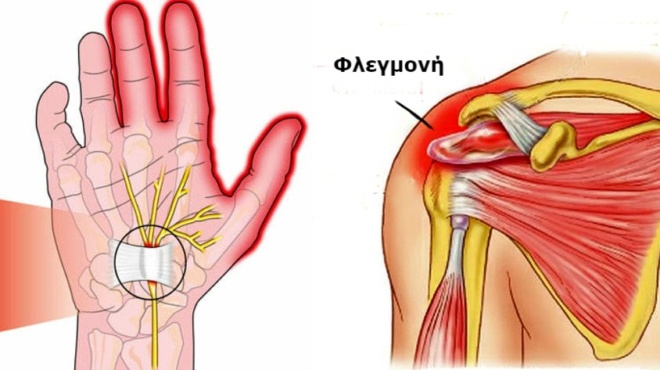

Η φλεγμονή εμφανίζεται σε έναν υγιή οργανισμό, μόνο λόγο της κακής διατροφής του. Δηλαδή, όταν εκείνος τρέφεται με τρόφιμα, τα οποία έχουν υποστεί επεξεργασία. Οι επεξεργασμένες τροφές αποθηκεύονται από το σώμα στο αίμα και στους ιστούς. Μάλιστα, αυτές αποθηκεύονται ως κολλώδεις ουσίες.

Ωστόσο, το ανοσοποιητικό σύστημα, δεν μπορεί να αναγνωρίσει τις προαναφερθείσες ουσίες. Γι’ αυτό τις καταπολεμά, προσπαθώντας με κάθε τρόπο να τις αποβάλλει. Η συγκεκριμένη προσπάθεια που γίνεται από τον οργανισμό λέγεται φλεγμονή και εκεί που υπάρχει φλεγμονή, το σίγουρο είναι πως υπάρχει και πόνος.

Συμβουλές υγείας: Επώδυνες καταστάσεις, που σχετίζονται με τη φλεγμονή